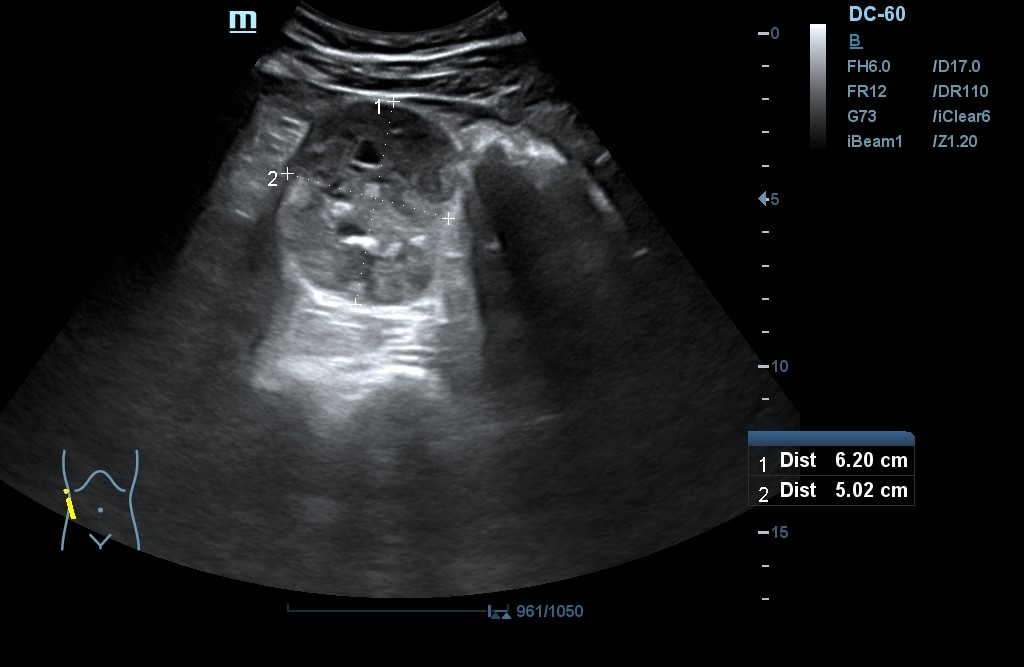

- POCUS: Lesión en polo inferior de riñón derecho (RD) de 6,2 x 5,02 cm de diámetro, con neovascularización y zonas hiperecogénicas. No signos de hidronefrosis. Disminución del flujo venoso con Doppler pulsado. Resultados compatibles con masa renal sólida a filiar. RI sin alteraciones. Jets vesicales presentes. Próstata de contornos regulares y ecogenicidad homogénea. Volumen prostático de 44 cm3.